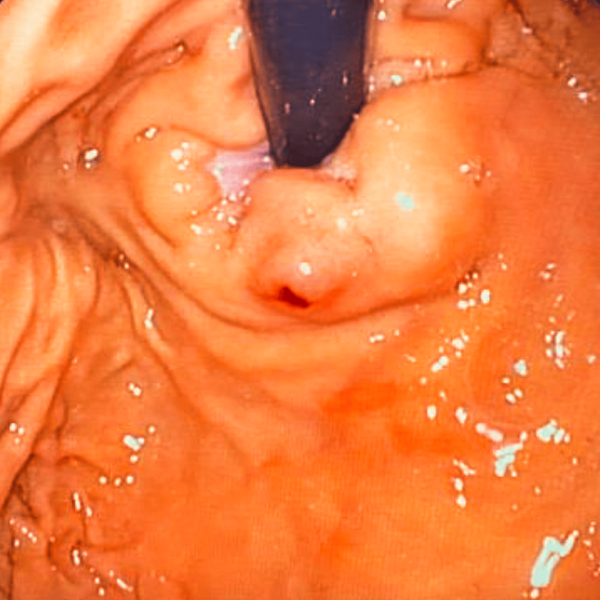

Lesión de Dieulafoy

La lesión de Dieulafoy constituye una entidad clínica particular dentro de las causas de hemorragia digestiva alta, caracterizada por la presencia de una anomalía vascular submucosa que mantiene un calibre…